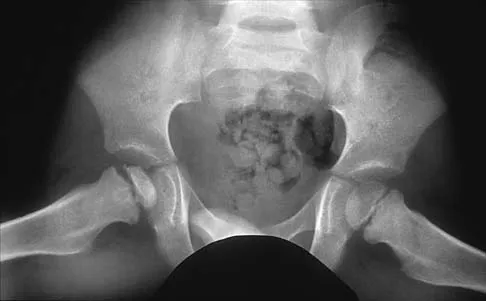

Question 80High Yield

A 3-year-old child has refused to walk for the past 2 days. Examination in the emergency department reveals a temperature of 102.2 degrees F (39 degrees C) and limited range of motion of the left hip. An AP pelvic radiograph is normal. Laboratory studies show a WBC count of 9,000/mm3, an erythrocyte sedimentation rate (ESR) of 65 mm/h, and a C-reactive protein level of 10.5 mg/L (normal < 0.4). What is the next most appropriate step in management?

Explanation